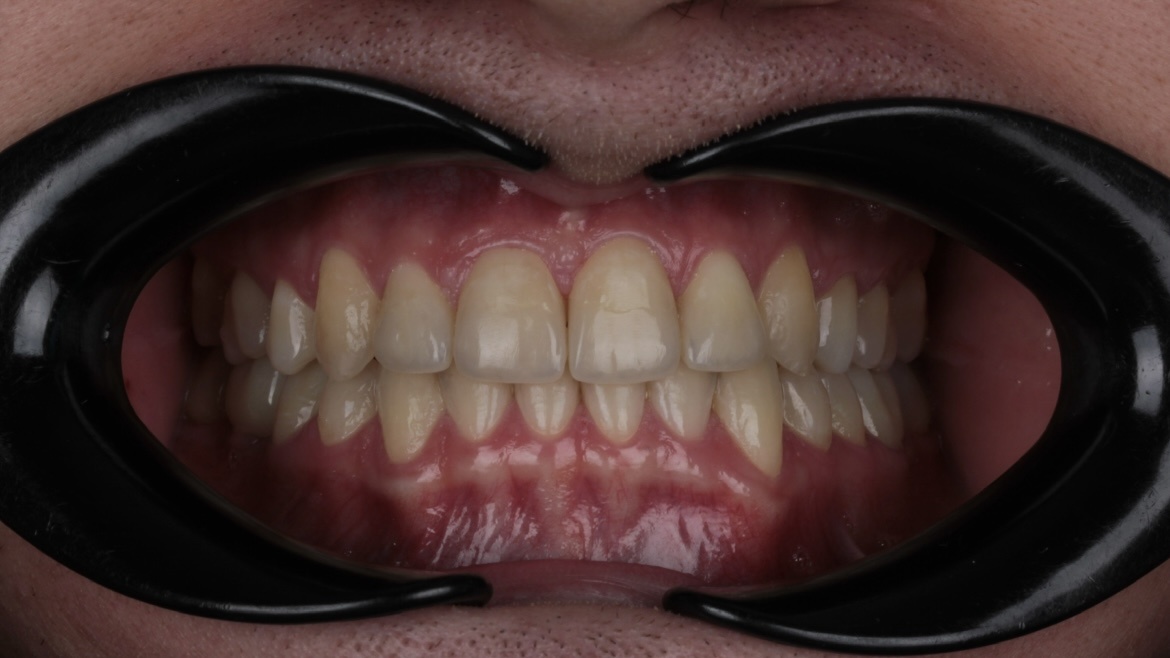

Пациент обратился в клинику «Два Дантиста» для восстановления эстетики зубов. Результат лечения его клинического случая — это совместная работа врача и пациента.

Джексенбаева Зарина Касымкановна, стоматолог-ортодонт, провела пациенту ортодонтическое лечение на элайнерах с использованием одного минивинта. Лечение длилось 2,5 года. По итогу получилось исправить прикус, скученность зубов, нормализовать контакты между верхней и нижней челюсти.

Также пациенту установили имплантат в месте отсутствующего зуба, на который Лукьяненко Артур Викторович, стоматолог-ортопед, зафиксировал керамическую коронку, восстановив целостность зубного ряда.

Кожокарь Карина Васильевна, стоматолог-терапевт, реставратор, с помощью композитного материала сделала реставрацию стертых единиц. Она нарастила края зубов, тем самым вернула единицам красивую и органичную форму.

Наш пациент проявил терпение и ответственное отношение на всех этапах восстановления: вовремя записывался на приемы, правильно носил элайнеры, выполнял все назначения врачей.